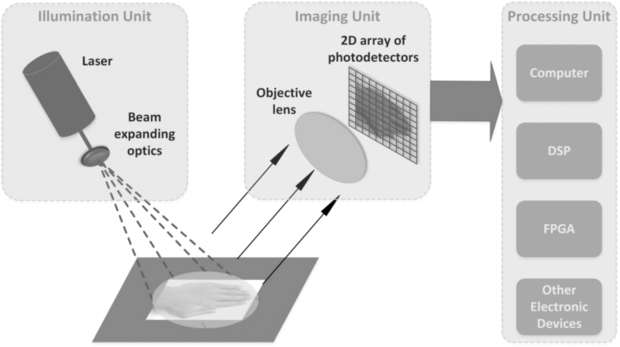

Standard image High-resolution imageBriers (2001) provided an excellent topical review on LDPI technology and applications for blood perfusion mapping and imaging for the formative years of the technique. His review also described the theory for the measurement of blood flow changes in the microvasculature. Laser Doppler imaging technology is now available in several forms, using the traditional raster scanning method and more recently line scanning technology (Nguyen et al 2011) and full-field imaging capability (Serov and Lasser 2005, Leutenegger et al 2011, He et al 2012) (figure 3). The imaging systems usually use a single operating wavelength, i.e. red or near infrared. Murray and co-workers (2004, 2005, 2009a) have shown the clinical value of using a red wavelength LDPI system in conjunction with a green laser and this is discussed further below.

Figure 3. Schematic diagram for full-field laser Doppler imaging technology concept. This approach enables fast scanning of areas such as the hands and synchronous changes across the field of view to be determined with confidence. (Courtesy of Professor S Morgan, Nottingham University.)